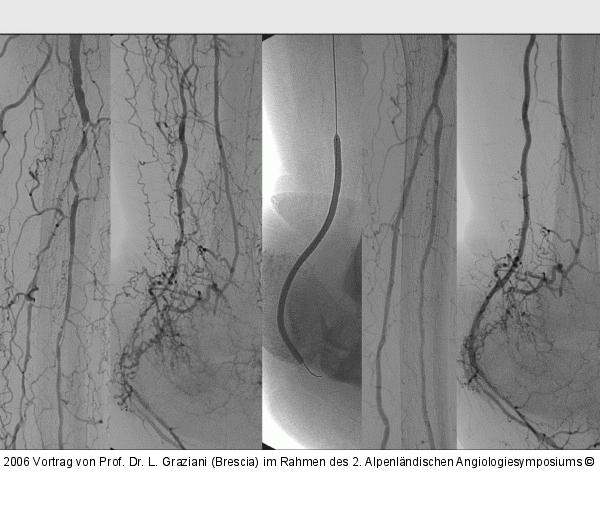

Vortrag von Prof. Dr. L. Graziani (Brescia) im Rahmen des 2. Alpenländischen Angiologiesymposiums

PTA of the foot arteries in diabetics: Extremities Extreme Angioplasty

Abbildung 40: PTA